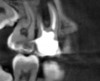

The patient stated that a previous root canal had been performed on tooth No. 18 many years ago, but he had no memory of the exact date or the name of the dentist who provided the treatment. The referring dentist had no records or preoperative radiographs of tooth No. 18 from before the initial endodontic treatment. A limited FOV CBCT scan of the tooth was taken, and a radiolucency was observed on the mesial and distal roots (Figure 4). The pretreatment pulpal diagnosis was "previously treated," and the periradicular diagnosis was symptomatic apical periodontitis.

The clinician determined that the treatment options were conventional endodontic retreatment or endodontic surgery, which would involve resectioning of the mesial and distal roots, preparation of the root ends, and placement of a bioceramic root-end filling. With regard to restorative evaluation, the existing crown on tooth No. 18 was deemed to be within normal limits. Although the periapical radiograph (Figure 3) showed a radiolucent line around the distal portion of the crown, the marginal integrity was determined to be clinically acceptable. The CBCT demonstrated that the inferior alveolar nerve canal was close in proximity to the mesial and distal roots of tooth No. 18. Also, clinically the surgical access around tooth No. 18 was limited for root-end resection endodontic surgery. The axial CBCT view showed that the current canal obturation was within normal limits (Figure 5).

CBCT sagittal view (lingual view exposure) of tooth N o. 18 revealed mesial

and distal root periapical radiolucency.

Fig 4.

CBCT axial view of tooth

No. 18 revealed canal obturation within normal limits.

Fig 5.